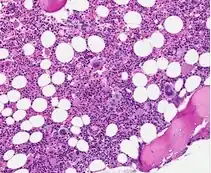

H&E of bone marrow in grade 0 Prefibrotic PMF